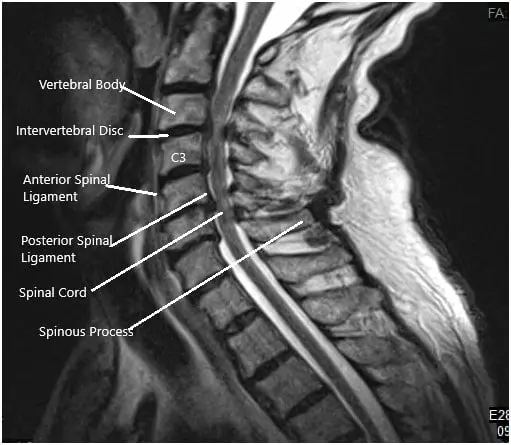

An MRI of the cervical spine suggested At C3-4, there is a central disc herniation with severe spinal canal stenosis and moderate compression of the cervical spinal cord, with compressive myelopathy. Disc protrusions are identified at C4-5 and C5-6 with moderate narrowing of the thecal sac and mild flattening/compression of the ventral cervical spinal cord. Mild narrowing of the thecal sac at C2-3 and C6-7, with a small central protrusion at C2-3.

Preoperative MRI in sagittal section.